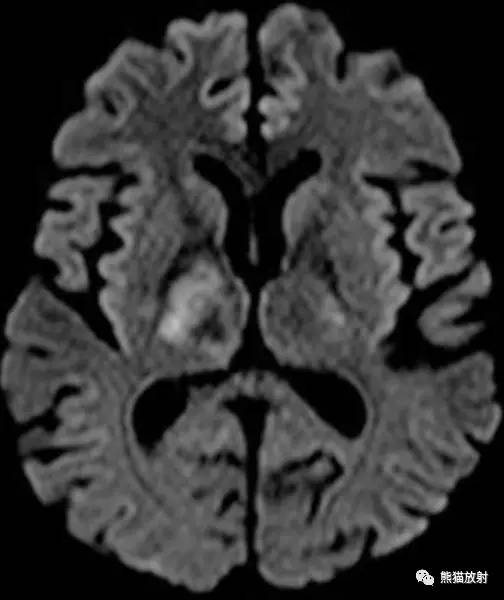

CASE 2

病史:患者男性,45 岁,进行性偏瘫,既往有酗酒、艾滋病、丙型肝炎病史。

FLAIR、DWI和 ADC图示:右侧放射冠和基底节区可见 T2 高信号病变,不伴有脑水肿,边缘部分扩散受限。

增强示病灶外缘轻度强化; MRS示 Cho 和 NAA 峰降低,脂乳酸峰值保留;免疫组化结果提示阳性染色为 JC 病毒。